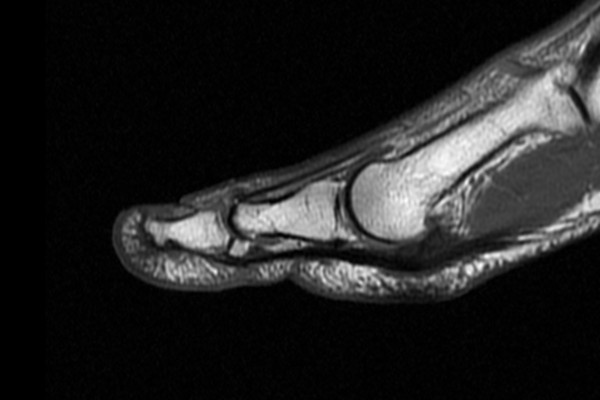

43세 남성환자분으로 좌측 엄지발가락 통증과 발가락이 잘 들리지 않는 증상으로 내원해주셨습니다.

내원 2일전 발가락이 아래로 꺾이면서 부딪히면서 다치셨다고 하셨고 발가락에 심한 피멍이 보였습니다.

X-ray 검사 시 이상이 발견되지 않았는데, 피멍이 들었다는거는 인대나 힘줄 등 무언가 파열되었을 때

나타나는 증상이기 때문에 MRI 촬영을 진행하기로 하였습니다.

b1d6a7ed823268faf8290a31a2d8a8bb_1765956466_3658.jpg

MRI 촬영결과 발가락을 들어올리는 힘줄인 장무지신전건(힘줄) 부착부 파열

(Lt. foot 1st toe Extensor Hallucis Longus (EHL) avulsion tear)이 확인되었습니다.